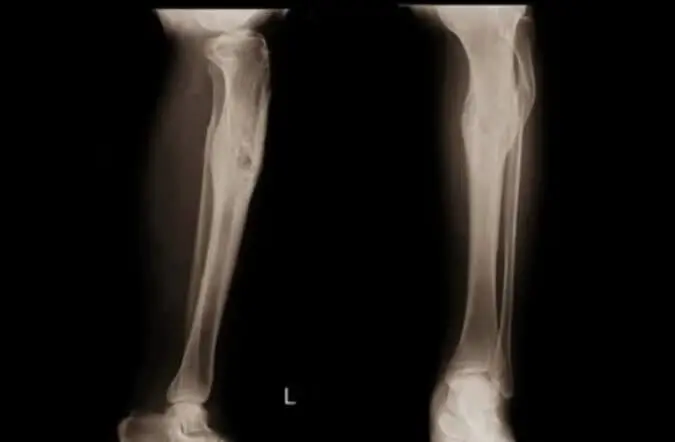

- Остеомієліт Гарре ділянки, який супроводжується болем в коліні;

- хвороба Осгуда-Шлаттера – остеохондропатія бугристості великої гомілкової кістки. Біль при цьому буде місцева в ділянці бугристості кістки;